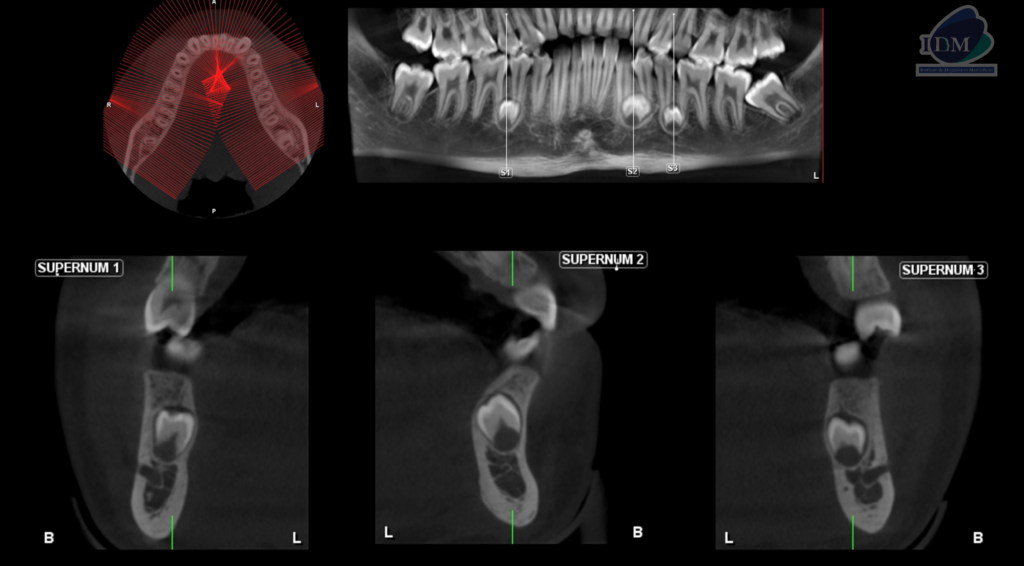

Así mismo en la tomografía volumétrica de haz se evidencia:

- Supernumerario 1: retenida en posición vertical y en contacto con los segmentos radiculares de las piezas 45 y 46, a nivel apical y orientado hacia lingual.

- Supernumerario 2: retenida en posición vertical y en contacto con los segmentos radiculares de las piezas 33 y 34, a nivel apical y orientado hacia lingual.

- Supernumerario 3: retenida en posición vertical y en contacto con los segmentos radiculares de las piezas 35 y 36, a nivel apical y orientado hacia lingual.

RECONSTRUCCIÓN 3D

Conclusión imagenológica:

- Presencia de tres dientes supernumerarios